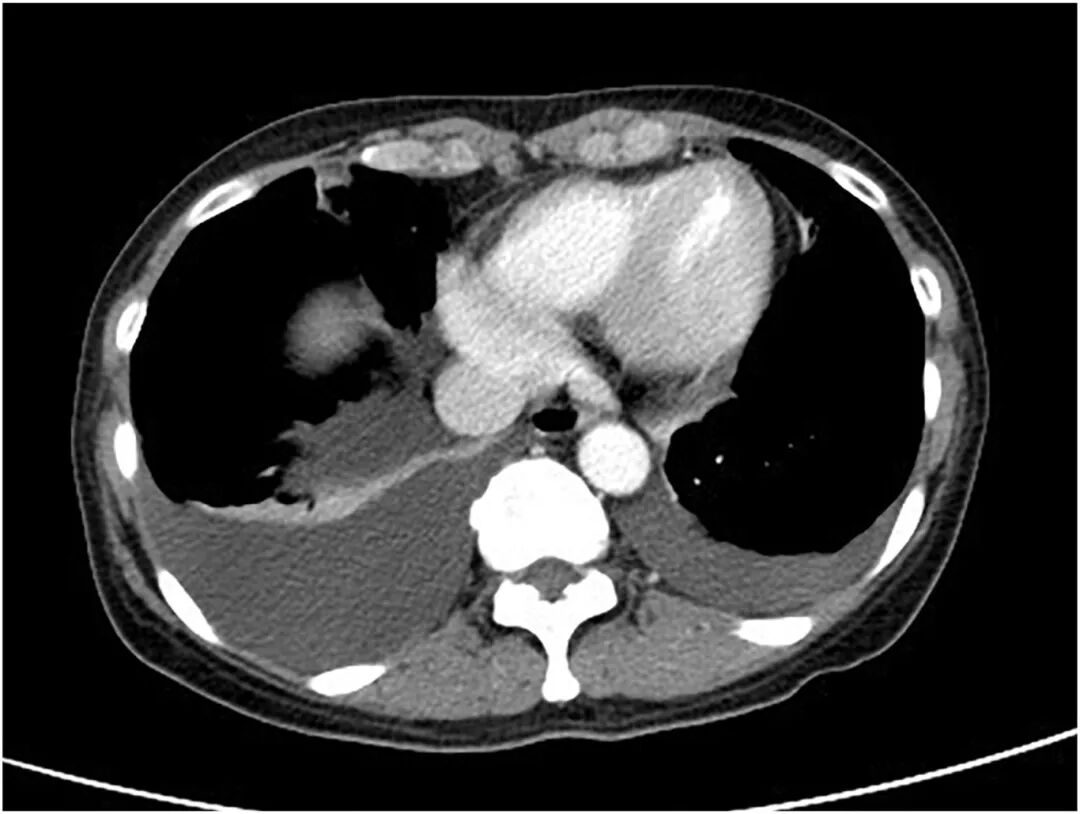

腹部计算机断层扫描(CT)显示盆腔内有一占位性病变,伴中等量腹水

及双侧胸腔积液

,且右侧较左侧更为明显(图2、图3)。

图3 CT检查

(横断位)亦可见双侧胸腔积液,右侧更为显著。